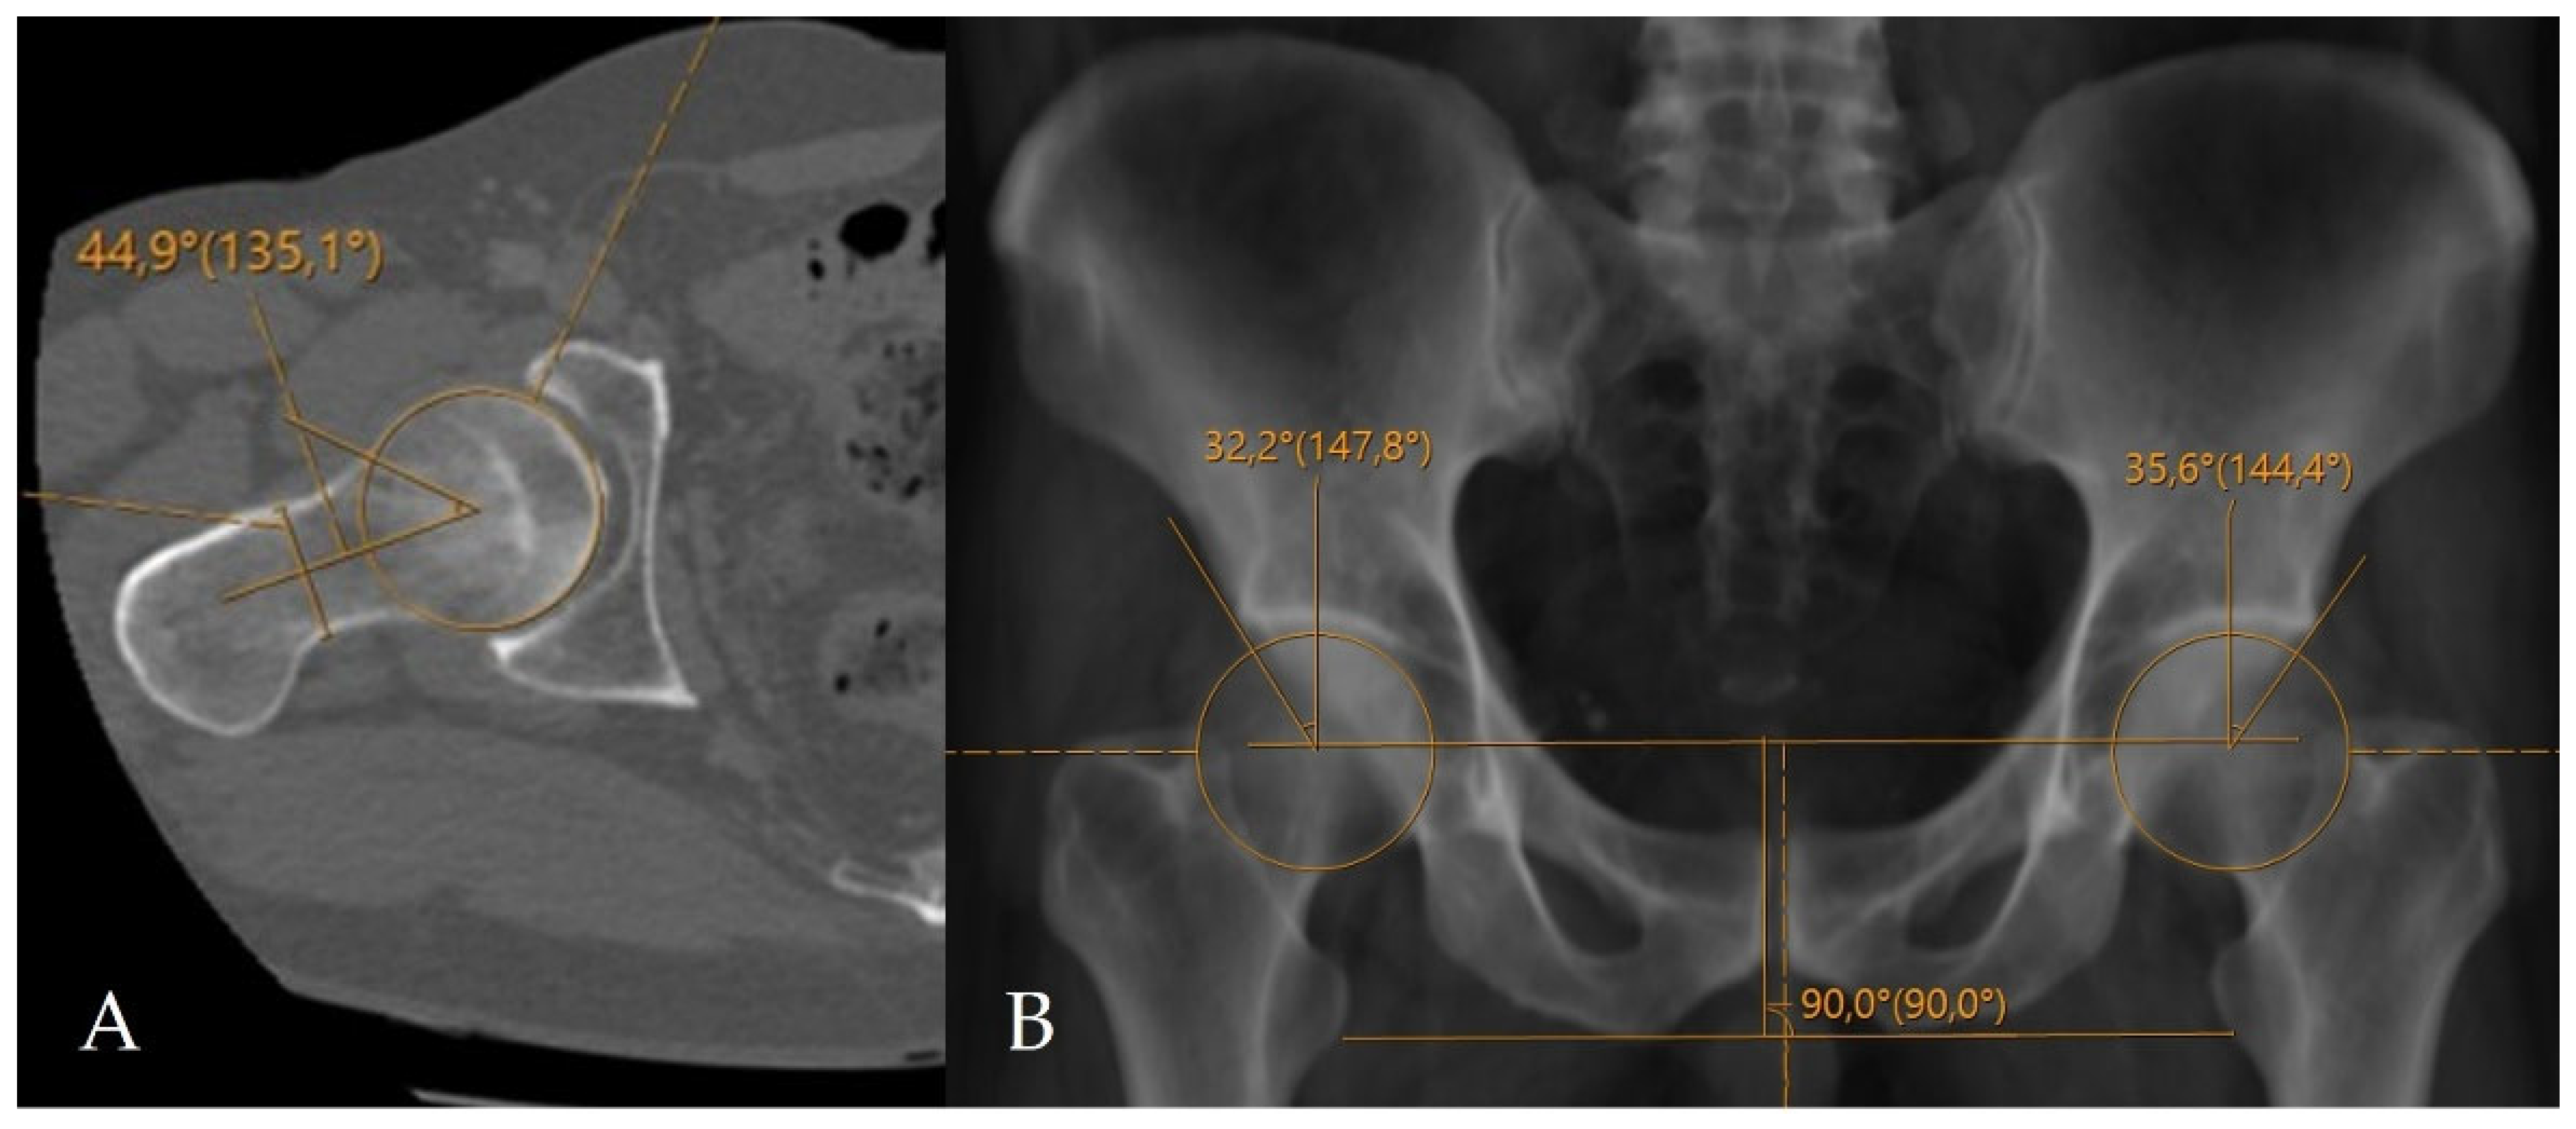

Figure 2. Application of conventional angular measurement methods on a radiology workstation. (A) Measurement of the alpha angle on axial oblique CT reformats. (B) Measurement of the LCEA on a CT-based virtual pelvic radiograph.

The alpha angle and lateral center–edge angle (LCEA) were measured on CT. The alpha angle was assessed on axial oblique CT reformats parallel to the femoral neck axis as described by Nötzli et al., and the LCEA was measured using the CT-based coronal three-dimensional (3D) virtual pelvis radiograph model as used by Ergen et al. [13,14]. Acetabular coverage index (ACI) values were subsequently calculated using CT-MIP reconstructions. In all cases, angular measurements were complemented by a comprehensive morphological assessment for the presence of FAI, including evaluation of the crossover sign, posterior wall sign, ischial spine sign, and anterior wall lateralization (Figure 2 and Figure 3). CT was further used to evaluate the morphology of the acetabular rim, and acetabular overcoverage subtypes were determined [15]. The presence of underlying FAI and its specific subtype were determined by two radiologists in consensus. All measurements were independently repeated by both radiologists at a four-week interval. The senior radiologist had 20 years of musculoskeletal radiology experience, whereas the general radiologist had 5 years of clinical radiology experience. Prior to the measurements, the general radiologist underwent a one-week training period under the supervision of the senior radiologist. Statistical analyses were performed using the measurements obtained by the senior musculoskeletal radiologist. To assess intraobserver reliability, the senior radiologist recalculated ACI measurements after a minimum interval of two months. Prior to initiating angular measurements, the entire dataset was reviewed and verified by an independent radiology resident after deletion of all previous measurements and anonymization of cases. Subsequently, cases were randomly ordered to minimize assessment bias and ensure objective analysis. For primary statistical analyses, measurements obtained by the senior musculoskeletal radiologist were used to reflect routine clinical practice, while the second reader’s measurements were used exclusively for interobserver agreement analysis.

Imaging data were retrospectively retrieved from the SECTRA PACS workstation (IDS7, version 24.2.16.6066; Sectra AB, Linköping, Sweden). Cam-type FAI was defined by an alpha angle of ≥60°, whereas pincer-type FAI was defined by an LCEA of ≥40° (Figure 4) [16,17,18,19]. For CT-MIP evaluation, the maximal cross-sectional area of the femoral head was initially measured on axial CT images using a circular region of interest (ROI). MIP reformatted images with a slab thickness of 10 mm were subsequently generated to enable a comprehensive single-slice evaluation of the acetabular roof. The acetabular coverage area was calculated by manual freehand delineation of the acetabular roof margins covering the femoral head, while preserving the femoral head contours. The ACI was defined as the ratio of the acetabular coverage area to the area of the femoral head (Figure 5).